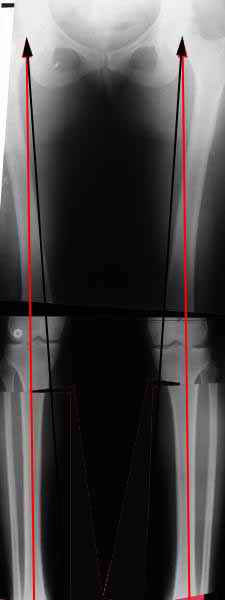

AVM> Александр, а не могли бы вы представить ваши схемы расчета? С учетом

Вот, с учетом и без учета, и на разных уровнях...

AC> Вот, с учетом и без учета, и на разных уровнях...

AC> Саша Артемьев, может, для данного случая свой вариант нарисуешь?

Из приведнной схемы не совсеим понял что означают разноцветные линии.

И зачем латерализация периферического фрагмента. Я всегда делаю медиализацию. См схему. И для данного случая медиализация подходит как нельзя лучше.

a> Из приведнной схемы не совсеим понял что означают разноцветные линии.

Черные - это нынешняя механическая ось. Красные - это планируемая правильная ось.

a> И зачем латерализация периферического фрагмента.

;-) Читайте Палея. Стр. 114-115.

a> Я всегда делаю медиализацию. См схему. И для данного случая

Медиализация - это чисто эстетический прием, как я понимаю. Поскольку если делать остеотомию ниже вершины деформации, для восстановления оси надо делать смещение по ширине, в данном случае как раз латерализацию.